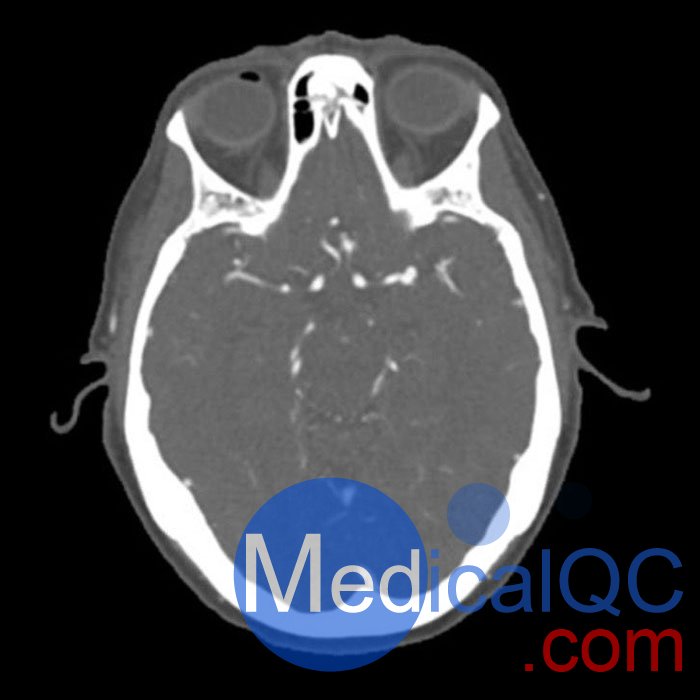

WEK50-03動脈瘤頭模,WEK50-03血管造影CTA頭模是頭部 CTA 動脈瘤模型

模擬造影劑動脈期頭部增強(qiáng)(CT血管造影)。 它覆蓋了頂點(diǎn)枕骨大孔。

模型有三個顱內(nèi)動脈瘤

大腦中動脈 (MCA) 的前部

交通動脈 (ACoA) 和基底動脈動脈。

該體??捎糜贑T(包括CBCT)評估和優(yōu)化成像性能和人工智能診斷。 這是也適合培訓(xùn)目的。

WEK50-03動脈瘤頭模,WEK50-03血管造影CTA頭模影像圖:

更多效果和DICOM數(shù)據(jù)請聯(lián)系我們